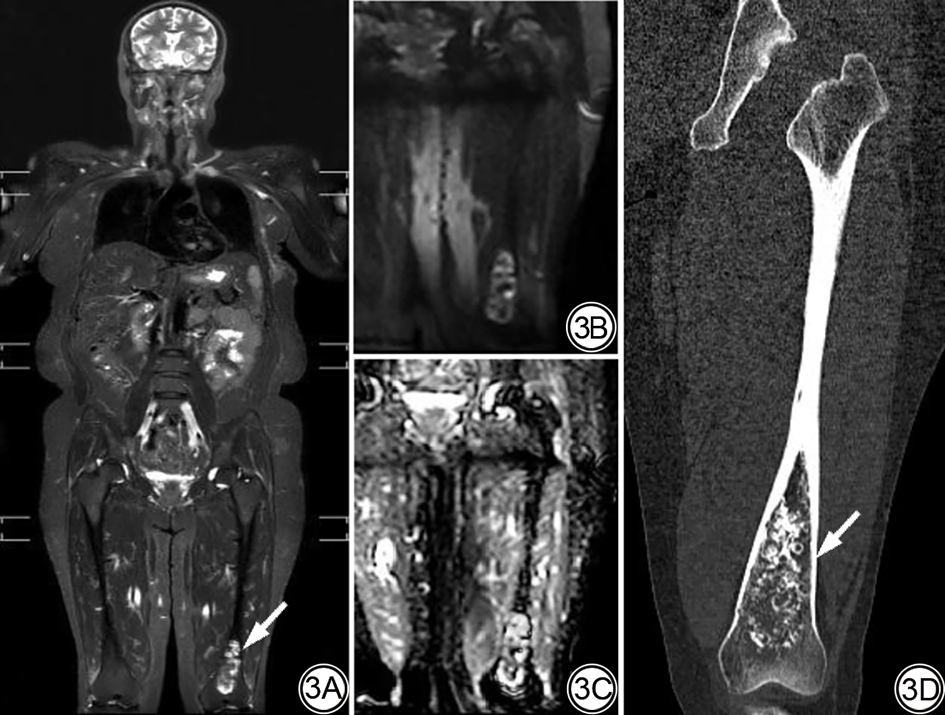

对有随访结果的116个显著病变的临床管理路径及最终结局进行归纳。极少部分病变(4/116,3.45%)因临床症状明显或影像提示恶性,最终接受了穿刺活检或手术切除:脑胶质瘤1例、脑膜瘤2例、肾透明细胞癌1例(图2)。但绝大多数(112/116,96.55%)通过常规影像学检查或随访被证实为良性或稳定性病变[如纵隔结节、肝脏海绵状血管瘤、脾脏血管瘤、胆系扩张、胰腺IPMN、肾脏错构瘤、子宫腺肌症、附件巧克力囊肿、骨岛、内生软骨瘤(图3)、臂丛神经水肿(图4)等]。

图4  女,65岁,左乳浸润性癌根治术后6个月。4A:WB-MRI的DWI序列MIP图显示左侧臂丛神经增粗肿胀(箭);4B:T2WI-STIR序列显示左颈部轻度软组织水肿(箭),为显著偶发病变,结合临床考虑为放疗后改变。WB-MRI:全身磁共振成像;DWI:扩散加权成像;MIP:最大密度投影;T2WI-STIR:短时反转恢复技术的T2加权成像。

Fig. 4  Female, 65-year-old, with invasive carcinoma of the left breast underwent radical surgery for 6 months. 4A: DWI sequence MIP map of WB-MRI showed thickening and swelling of the left brachial plexus (arrow); 4B: T2WI-STIR sequence shows mild soft tissue edema in the left neck (arrow), which is a significant incidental lesion, and it is a change after radiotherapy in combination with clinical considerations. WB-MRI: whole-body magnetic resonance imaging; DWI: diffusion-weighted imaging; MIP: maximum density projection; T2WI-STIR: T2-weighted imaging with short-time inversion recovery technique.